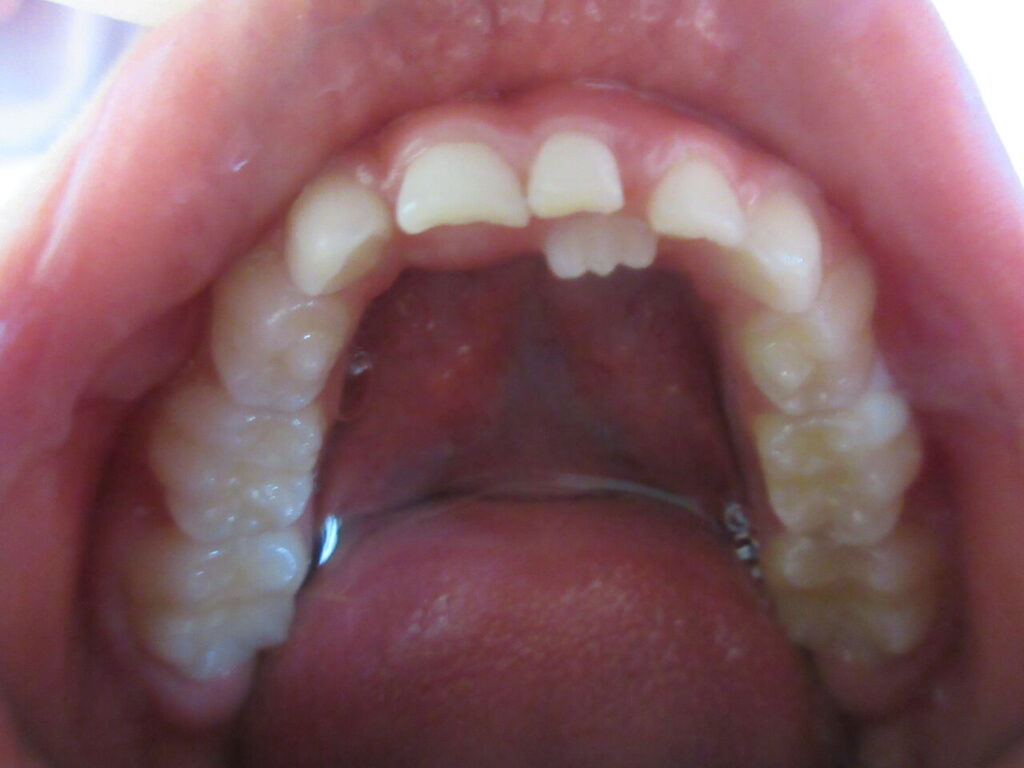

乳歯が抜けないうちに大人の歯が生えてきたと来院されました。

このようなケースは乳歯を抜歯すれば自然と永久歯が前に出て来ますが、スペースがない場合、前に出て来ませんので床矯正でスペースを作ればいいと思います。